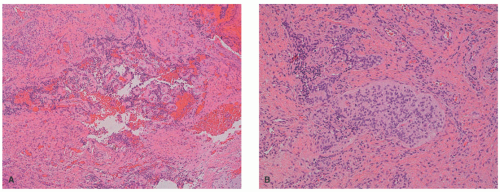

One of the consistent histologic features if the biopsy includes the subcutis is the near total replacement of the dermis and infiltration of the subcutaneous fat (Figure 24-26). The latter finding is not specific to DFSP because it is also present in diffuse NF and some of the fibrous tumors in an infant or young child. The classic pattern of DFSP consists of uniform, compactly arranged, spindle cells in fascicles and/or storiform profile, which replace the dermis and extend in a confluent fashion into the subcutis (Figure 24-27A-C). Fusiform cells have uniform nuclei with minimal pleomorphism and sparing mitotic activity. In addition to this basic pattern, myxoid and/or collagen-rich foci may be seen as adjoining foci with the classic pattern or as the exclusive pattern in some cases. The presence of scattered multinucleated giant cells in clefted or pseudovascular spaces in a spindle cell background or loose fibrous stroma are the features of GCF (Figure 24-28A-C). The GCF pattern can be localized in a DFSP with classic or fibrous features, may represent the exclusive pattern, or is present as the initial histologic feature in a tumor that recurs with classic, myxoid, or fibrous features.113 Pigmentation of tumor cells is uncommonly present in DFSP in the so-called Bednar tumor. Immunohistochemistry is a useful adjunct to the diagnosis of DFSP as long as it is understood that other dermal and subcutaneous spindle cell tumors are CD34+.122 Typically, CD34 staining is uniformly and diffusely positive (Figures 24-29 and 24-30), but other markers have been reported to facilitate the diagnosis including CD99, D2-40, and apolipoprotein

FIGURE 24-26. A-C, Dermatofibrosarcoma protuberans. Fibrohistiocytic proliferation with near total replacement of the dermis and infiltration of the subcutaneous fat (A). Uniform, compactly arranged, spindle cells in fascicles and/or storiform profiles that replace the dermis and extend in a confluent fashion into the subcutis (B and C). Digital slides courtesy of Path Presenter.com.

FIGURE 24-27. A-D, Dermatofibrosarcoma protuberans on the trunk of a 4-year-old male. A, Infiltration of tumor into the subcutis shows the overgrowth pattern. B, Another focus of this tumor shows a similar overgrown pattern, but note its more fibrous, hypocellular appearance. C, This focus shows scattered, enlarged tumor cells. D, The so-called honeycomb pattern of tumor growth is present in this focus.

FIGURE 24-28. A-C, Giant cell fibroblastoma (GCF) presenting in the breast of a 7-year-old female. A, Numerous multinucleated giant cells with pericellular clear space are accompanied by a neoplastic fibrous stroma. B, Another area in the same neoplasm shows a diffuse fibrous pattern of this tumor. Most GCFs arise in a similar fibrous pattern. C, This GCF from the trunk of a 4-year-old male shows the exaggerated pseudoangiectoid pattern.